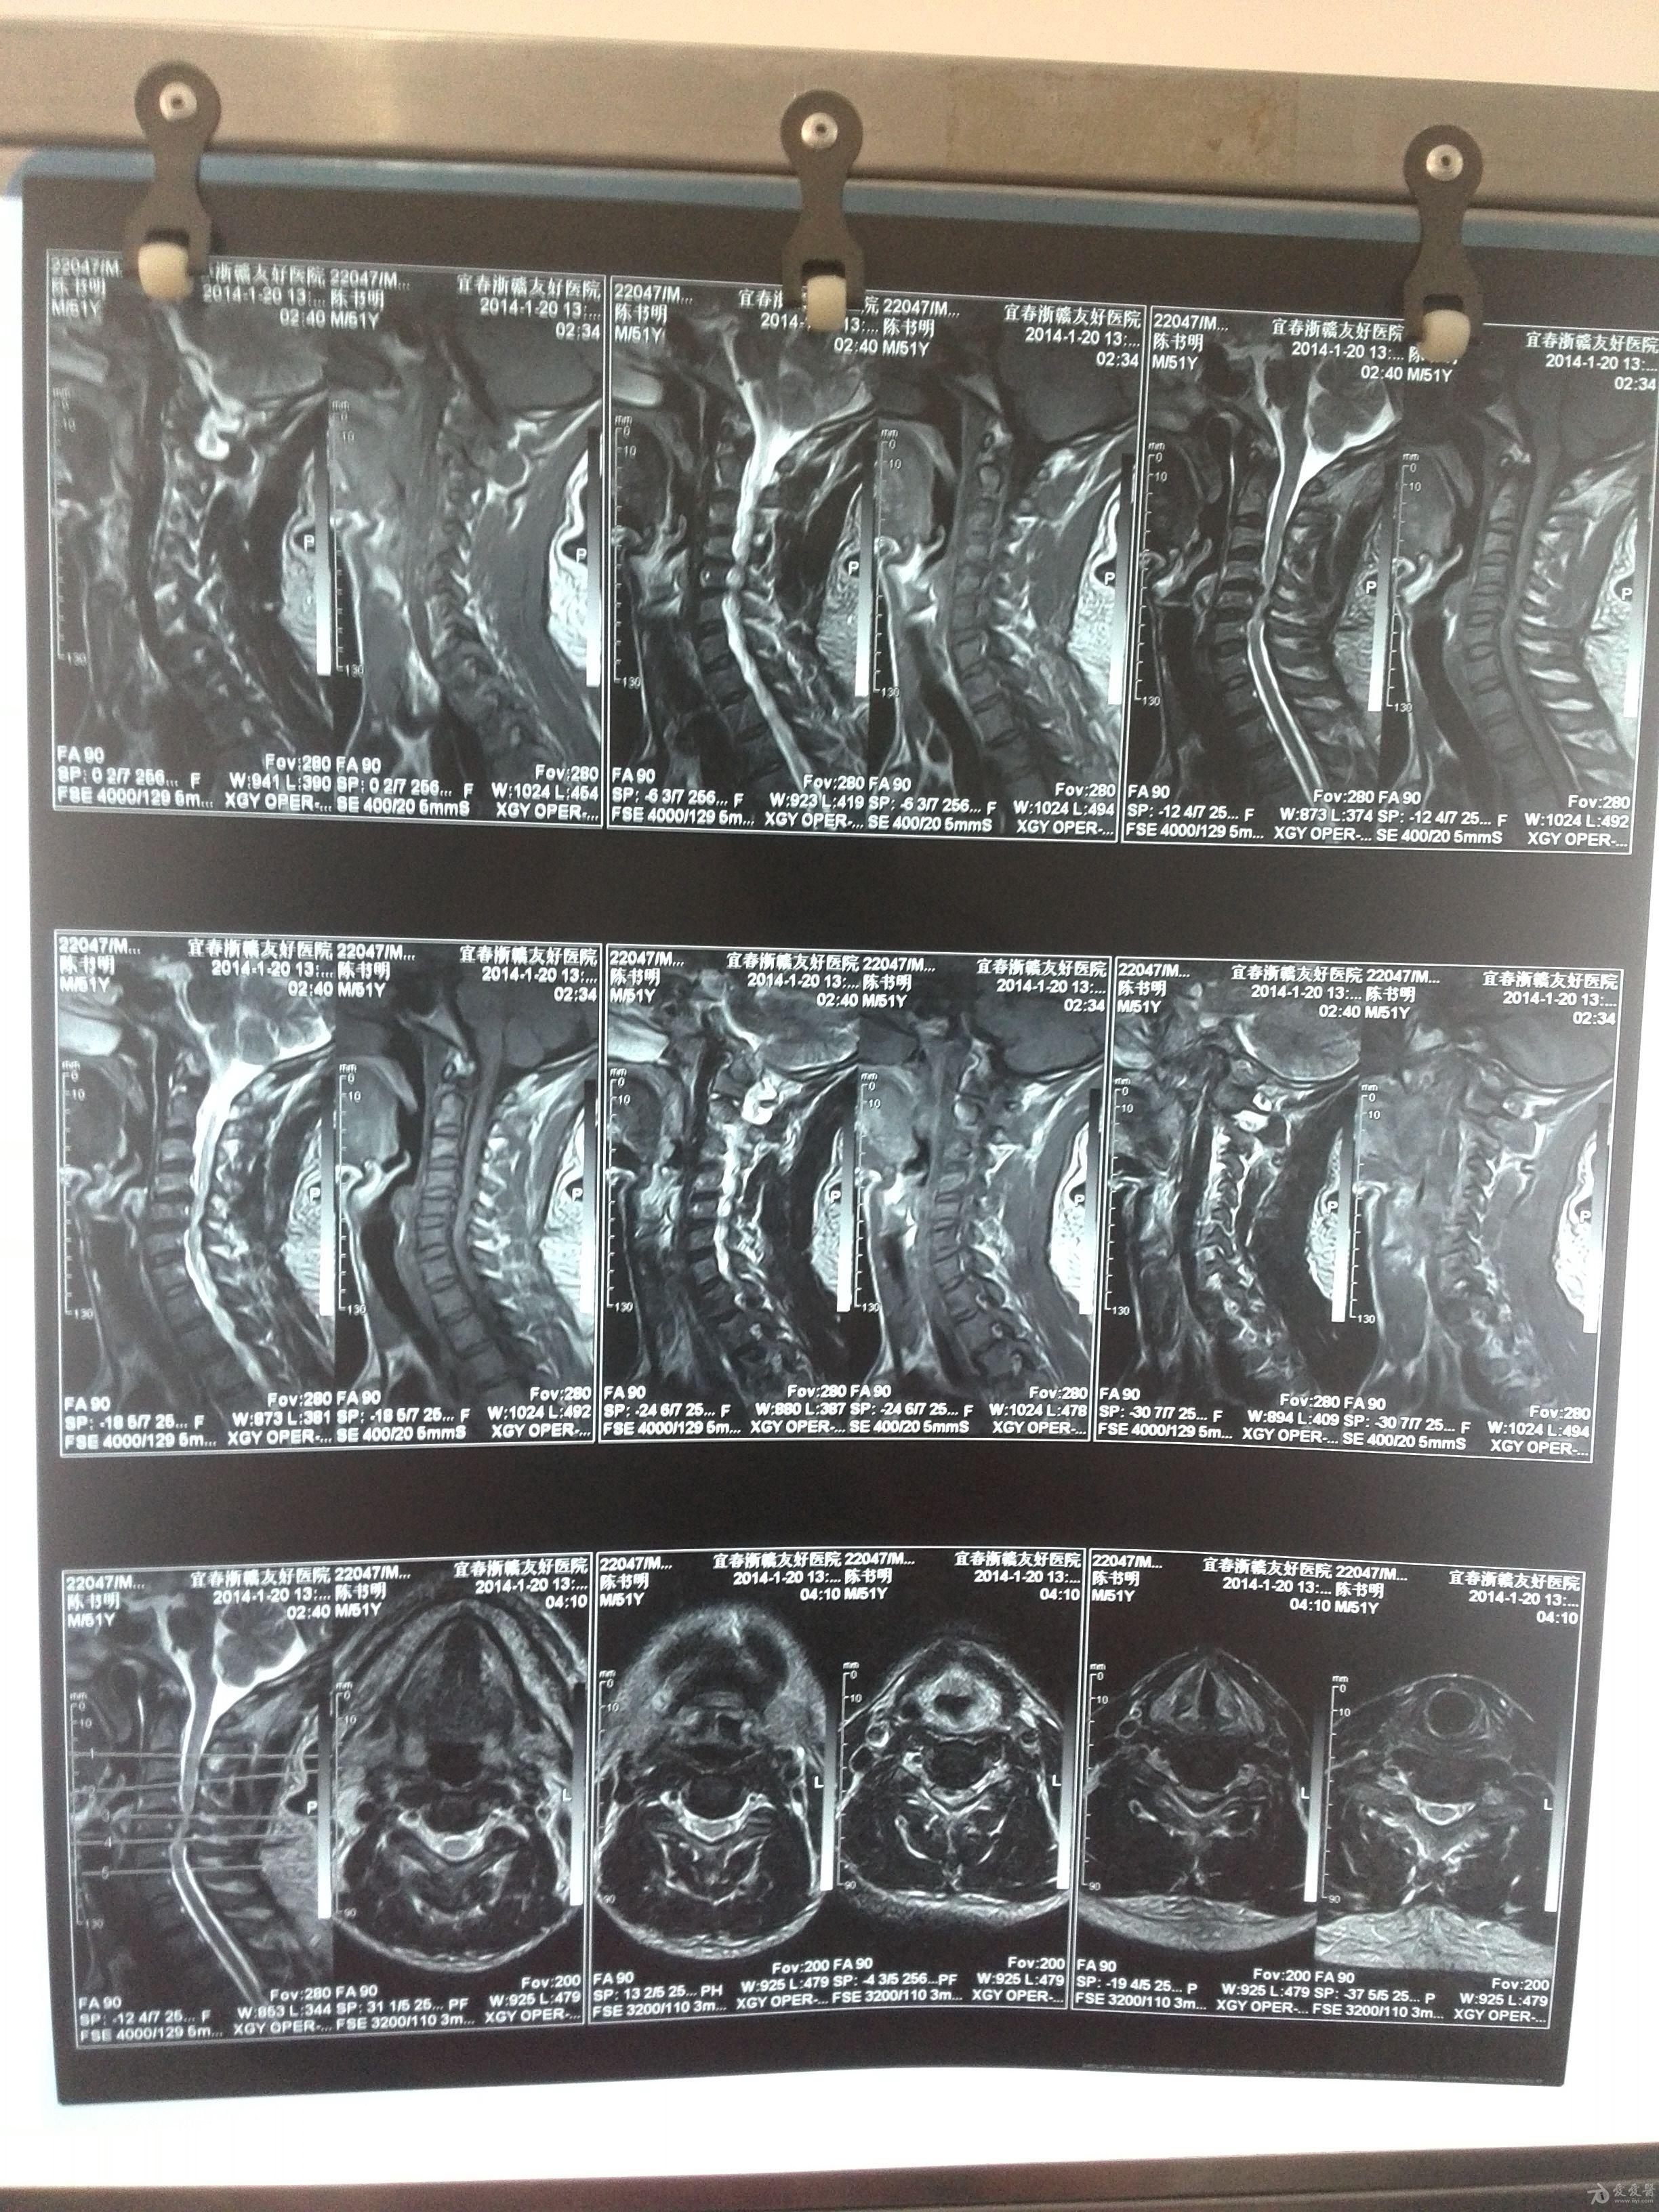

颈椎椎管狭窄 有图有真相

图片尺寸2448x3264